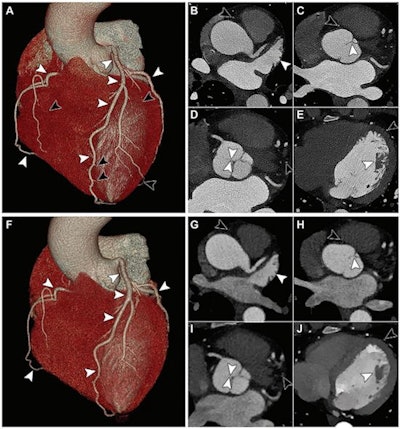

The research included 14 individuals with coronary artery disease who underwent electrocardiographically gated, contrast-enhanced CCTA on both a clinical prototype photon-counting CT device and a typical energy-integrating detector dual-layer CT system. Three cardiac radiologists read the exams and evaluated them for image quality, diagnostic confidence, and diagnostic quality of any features such as calcifications, stents, and noncalcified plaques using a five-point scale (1 = insufficient, 5 = excellent).

The group found that overall scores for image quality and diagnostic confidence were higher on the photon-counting CT images compared with images produced by a conventional CT system (5 vs. 4). Expressed in percentage of quality score improvement, the group reported the following: